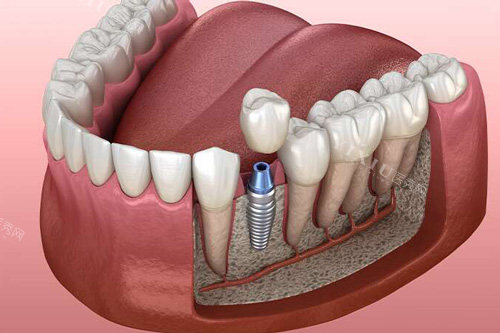

随着种植牙集采政策的超全落地,国产种植体品牌迎来了理想的发展机遇。2025年,国内种植牙市场呈现出进口品牌与国产品牌同台竞技的态势,其中登德玛、卓仕优、钛特利三大品牌凭借差异化优势脱颖而出,成为消费者关注的焦点。

作为温州头一个获得植入类三类医疗器械注册批文的本土企业,卓仕优在技术合规性上建立了显著优势。2024年7月,其总部在我国基因药谷西区正式开工,并与美皓医疗集团达成战略合作,进一步强化了研发与临床应用能力。卓仕优种植体采用医用纯钛材质,在生物相容性和骨结合效率上表现突出,特别适合对种植精度要求较高的前牙美学修复区域。其核心优势在于严格遵循各国医疗器械生产标准,为患者提供安心可靠的种植解决方案。

登德玛在国产种植体中以材料创新著称,主打四级钛合金种植体系统。该品牌通过优化钛金属的纯度与强度配比(钛纯度达99.5%以上),显著提升了种植体的抗疲劳性和耐腐蚀性,在复杂骨质条件下的长期稳定性表现优异。相较于传统纯钛种植体,登德玛的四级钛材质在力学性能上更接近进口高端品牌,但价格仅为后者的60%-70%,成为追求品质与性价比平衡患者的优选。近期行业检测报告显示,其材料标识真实性与实际性能高度一致,规避了部分进口品牌存在的"材质虚标"问题。

钛特利精密定位大众市场,以"让种植牙走进寻常百姓家"为理念,构建了非常有竞争力的价格体系。该品牌采用二级纯钛材质,通过简化生产工艺和规模化生产,将单颗种植体价格控制在集采政策的中低位区间,比登德玛低约30%。虽然钛纯度略低于四级钛产品,但其独特的表面处理技术仍能确保良好的骨结合结果,特别适合后牙功能区修复及预算敏感型患者。在2025年国产种植体品牌榜单中,钛特利凭借"基础性能可靠+价格亲民"的组合优势,占据销量前三位置。

三大品牌各有千秋,选择时需综合考量三大核心因素:一是口腔条件,前牙美学区建议优先卓仕优,后牙功能区可考虑登德玛或钛特利;二是经济预算,追求长期稳定性选登德玛,重视性价比选钛特利;三是医生建议,可靠口腔医生会根据牙槽骨密度、咬合关系等个性化因素推荐适配方案。值得注意的是,种植牙成功与否不仅取决于种植体本身,更依赖医生技术水平和术后维护,选择正规医疗机构和经验充足的医生至关重要。